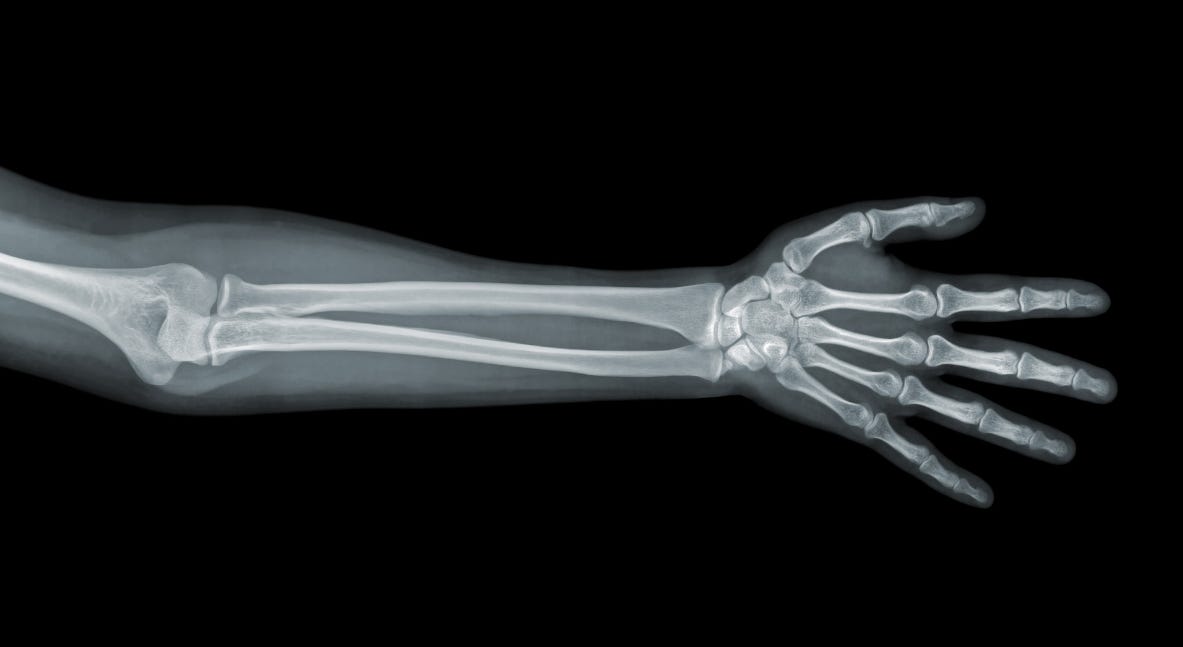

The X-ray

On a New Kind of Rays (1896)

In the winter of 1895, a German physicist named Wilhelm Conrad Röntgen made a discovery that would forever change medicine, physics, and our very perception of the invisible world. His paper, On a New Kind of Rays, outlined a series of experiments that revealed the existence of previously unknown radiation capable of penetrating solid matter and creating images of hidden structures.